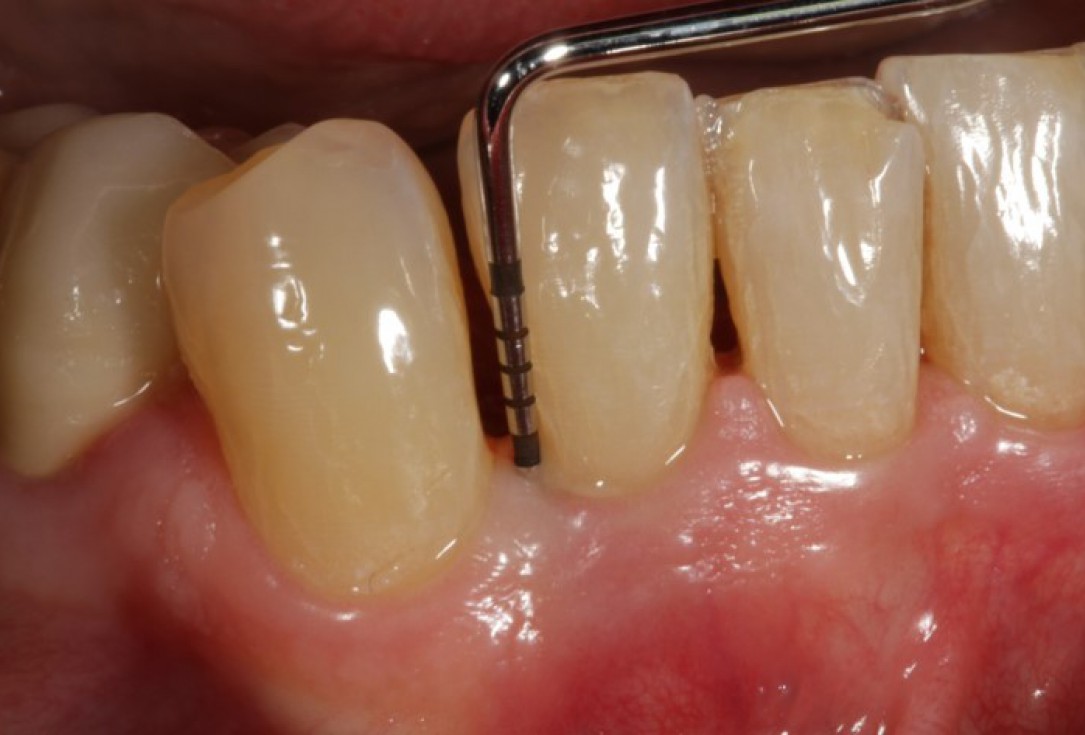

01/08 - Pre-operative clinical situation.

Non-contained intrabony defect treated using Straumann® Emdogain® and a synthetic bone grafting material - Prof. Dr. Dr. A. Kasaj